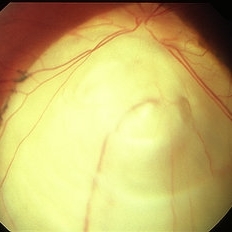

Coloboma

Coloboma

Mar 29 2013 by Henry J. Kaplan, MD

Coloboma involving optic nerve and inferior choroid.

Condition/keywords: coloboma of choroid, coloboma of optic disc